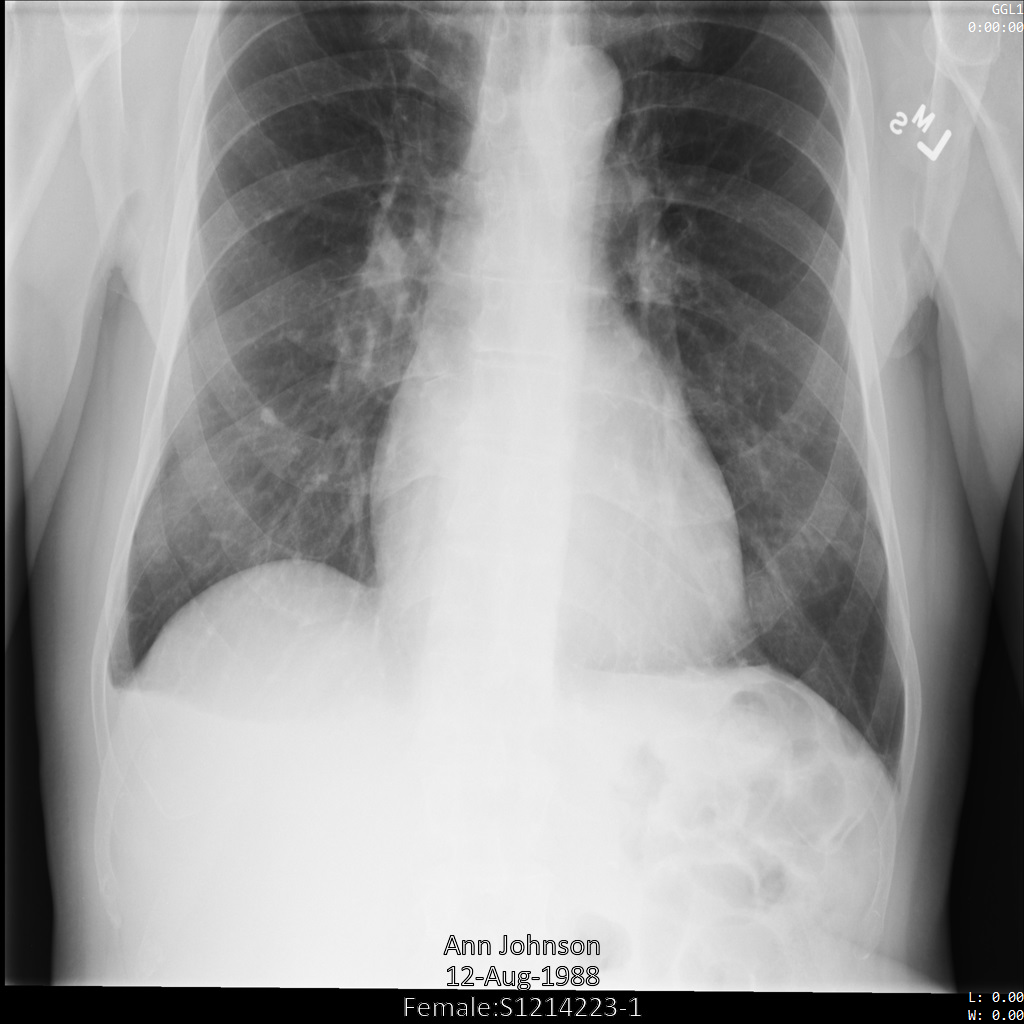

Después de enviar la imagen a la API de Cloud Healthcare mediante el perfil de filtro de etiqueta ATTRIBUTE_CONFIDENTIALITY_BASIC_PROFILE, la imagen aparece de la siguiente manera. Mientras se ocultan los metadatos que se muestran en las esquinas superiores de la imagen, permanece la PHI quemada que se encuentra en la parte inferior de la imagen.

Para quitar también el texto grabado, consulta Cómo ocultar el texto grabado de las imágenes.